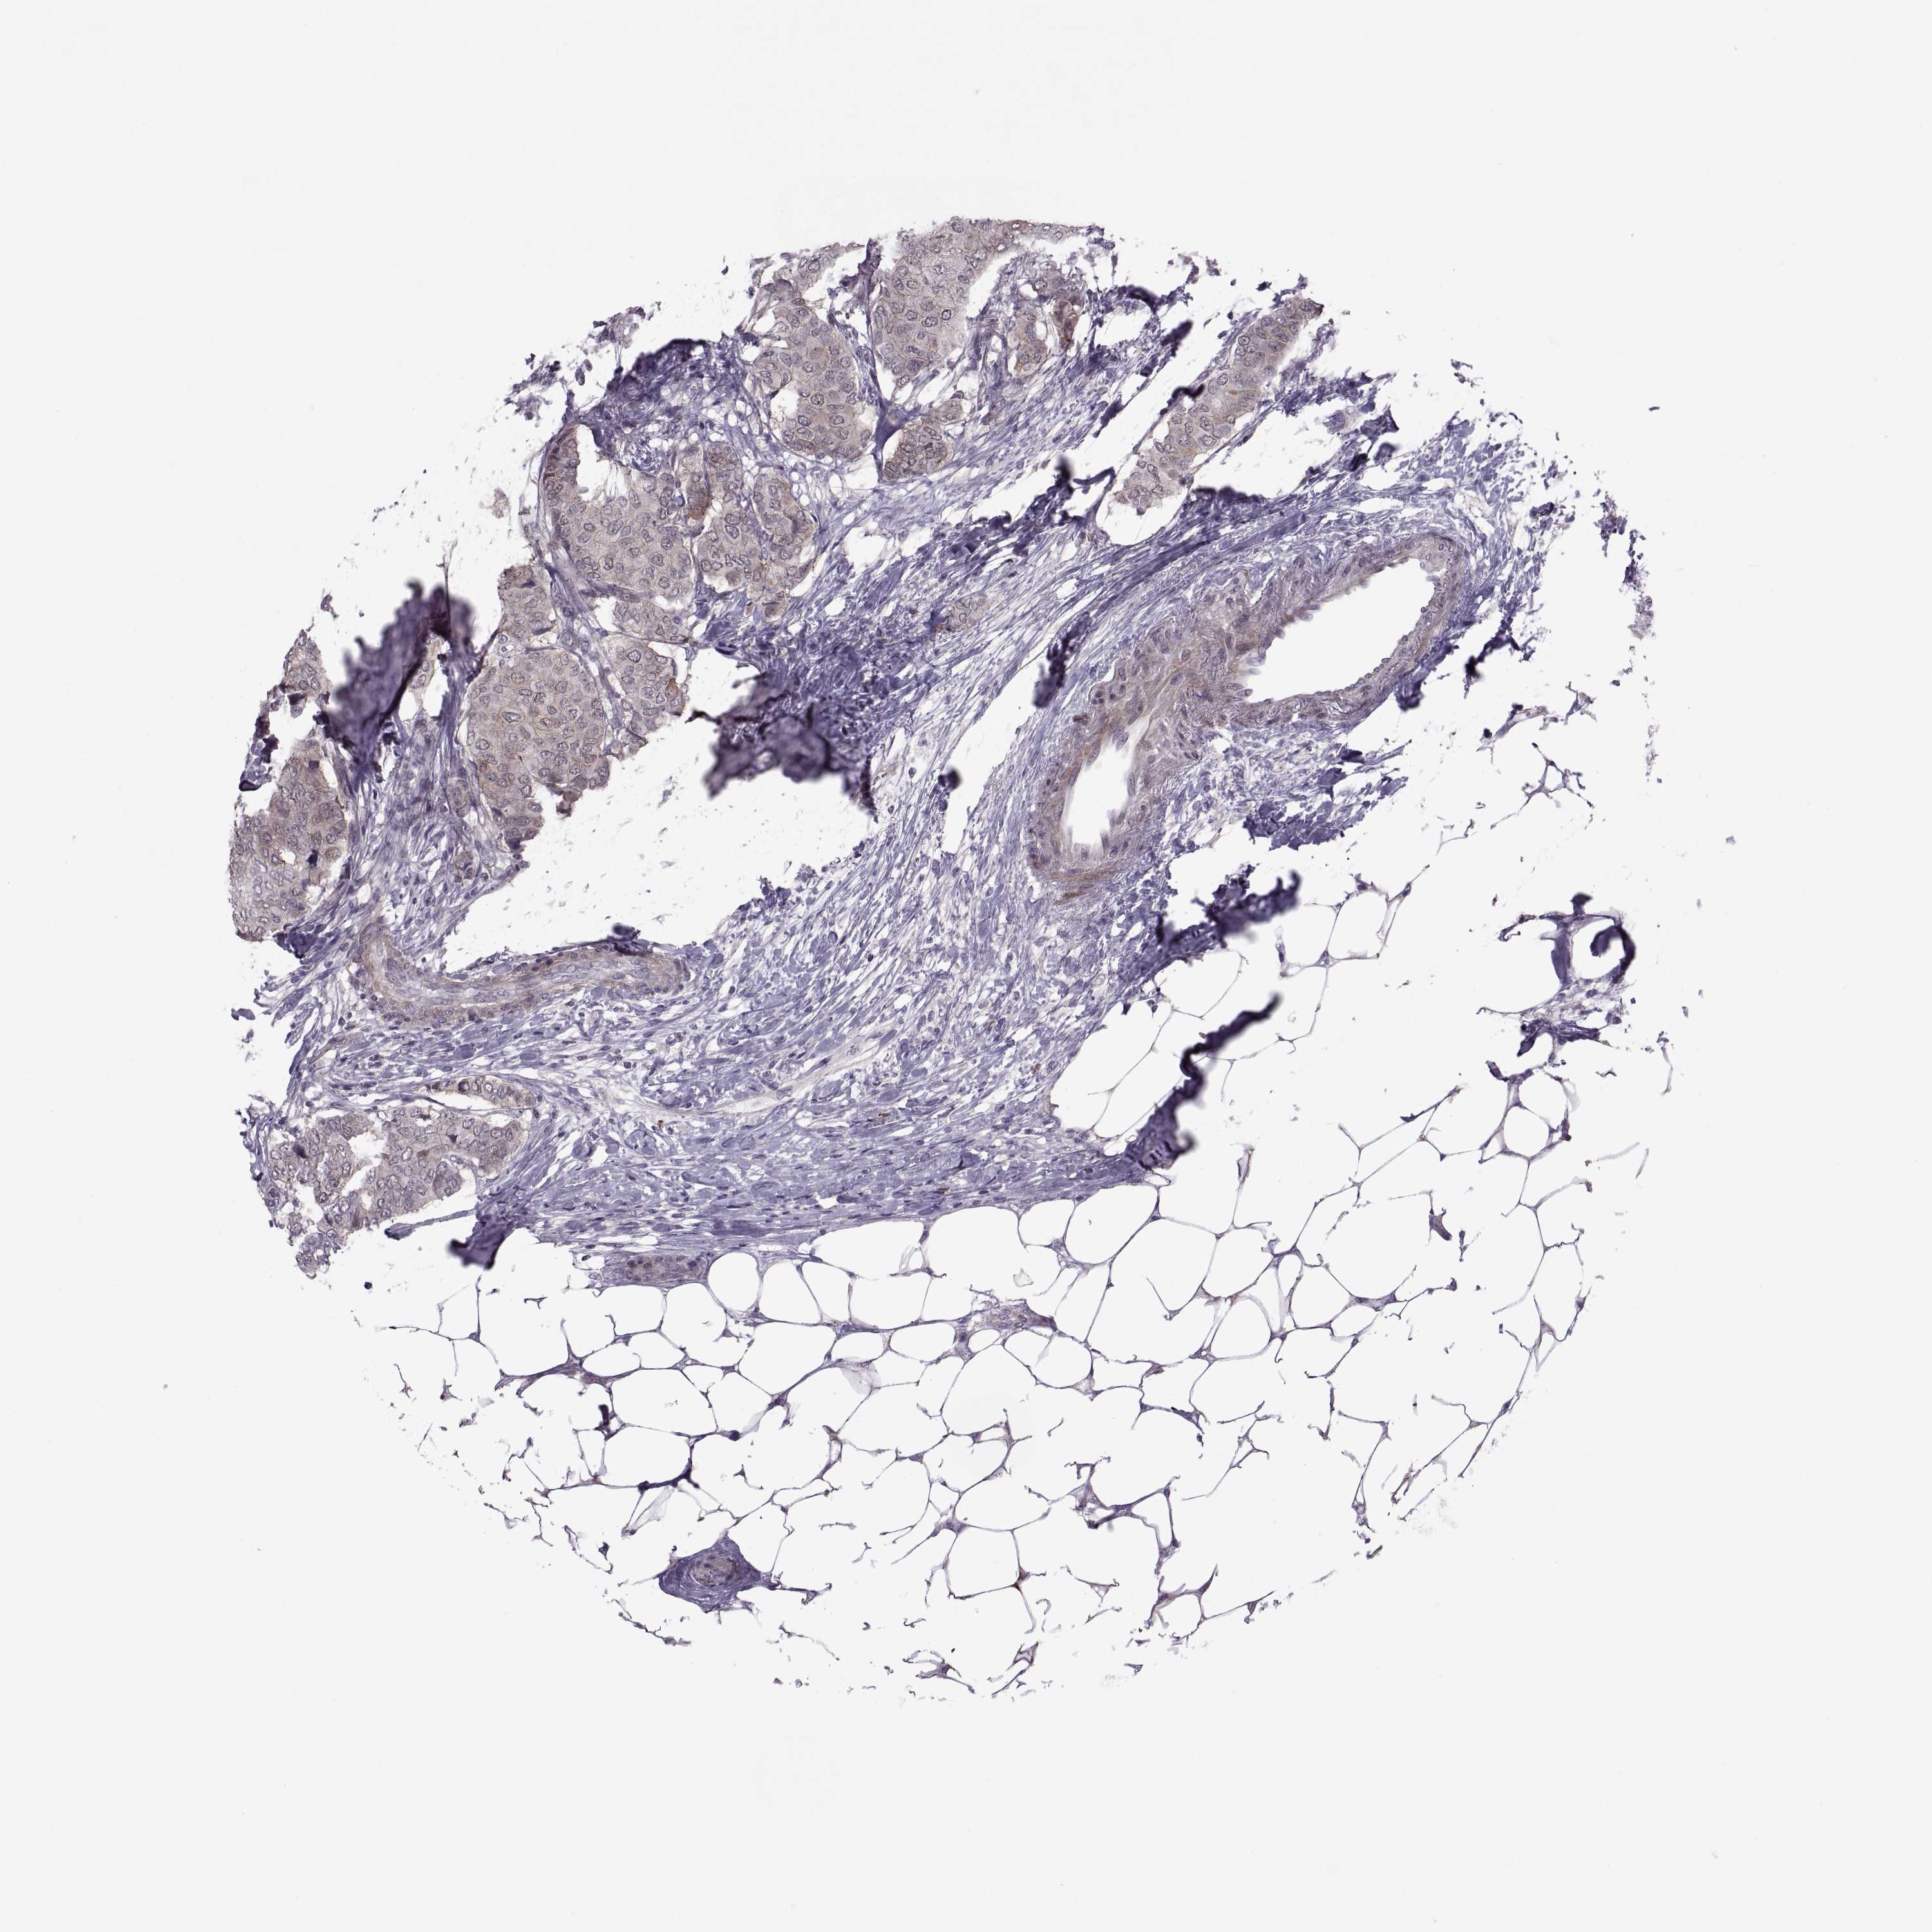

CANCER BREAST CANCER Show tissue menu

BRCA TCGA BRCA VALIDATION PROTEIN EXPRESSION

Breast cancer

Human cancer